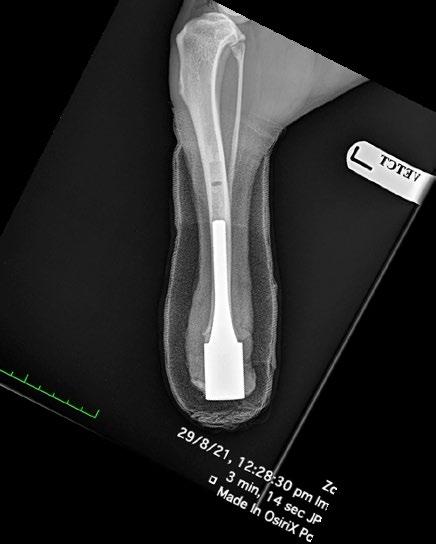

Osseointegrated Transcutaneous Amputation Prostheses in Veterinary Medicine

Daniel R James